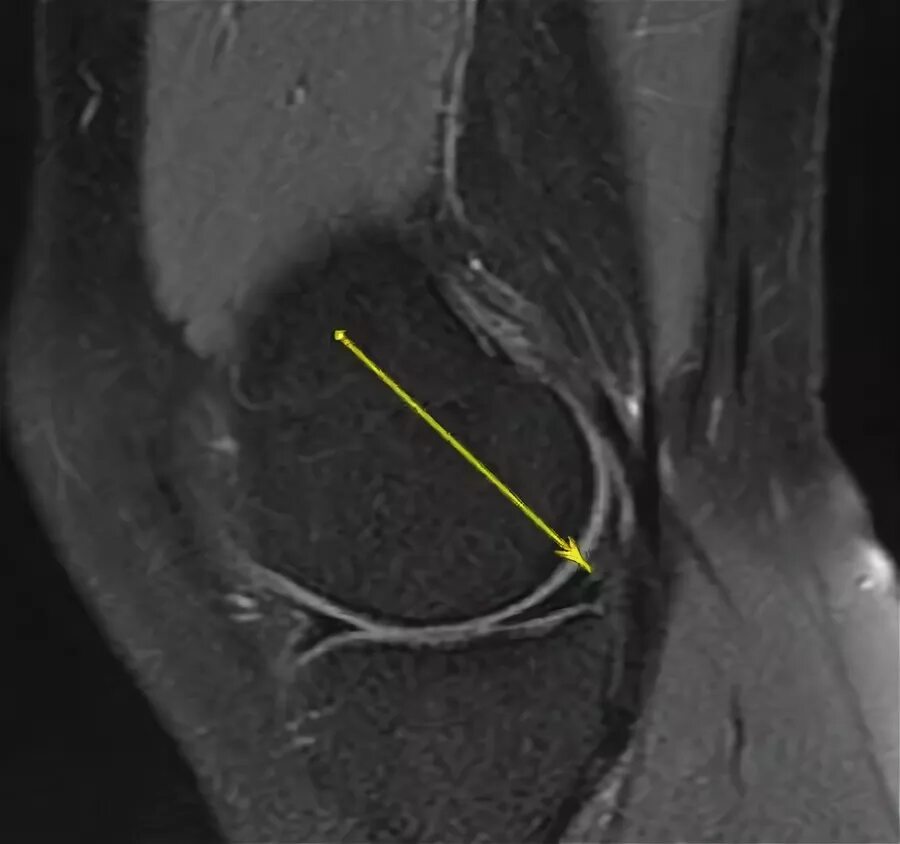

Разрыв мениска коленного мкб 10